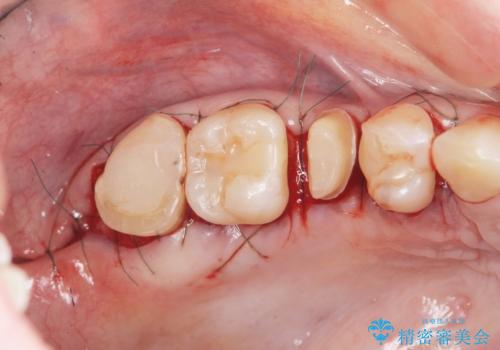

放置した虫歯を外科を行い抜歯を回避

- 放置していた虫歯が欠け、いよいよ怖くなり治療を希望され来院されました。

虫歯は、その進行度によりさまざまな治療法が提案されますが、

エナメル質・象牙質に限局する虫歯 →インレー修復

歯の神経に達する虫歯 →根管治療 クラウン補綴

歯ぐきよりも深い虫歯 →歯周外科による歯周環境の整備

を適宜行うことで良好な結果を得ることができます。

症状に応じて適切な処置を行ったことで、抜歯を回避し良好な結果を得ることができました。